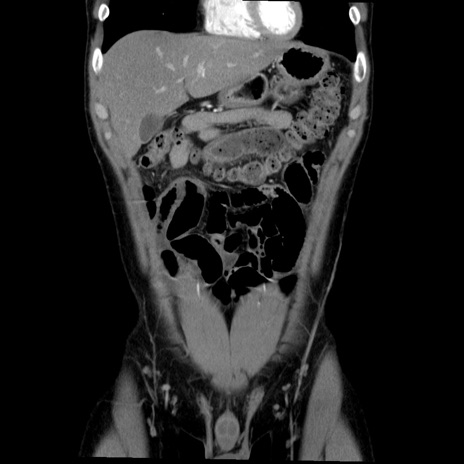

症例36(冠状断像)

【症例】20歳代 男性

【主訴】心窩部痛

【現病歴】今朝より上腹部痛あり。一旦軽快していたが再度出現したため救急要請。昨日夕に白身の魚を含む刺身を食べた。

【身体所見】BP 136/89mmHg、HR 74/min、BT 37.0℃、腹部:膨満、軟、心窩部に圧痛あり。反跳痛なし、筋性防御なし、腸雑音やや亢進あり。

【データ】WBC 17700、CRP 0.48